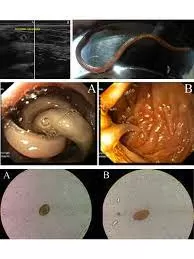

شكل دودة الاسكارس في البراز

دودة الإسكارس تبدو في البراز كدودة طويلة، بيضاء أو صفراء، وقد تكون حية وتتحرك أو ميتة وثابتة. يمكن أن يصل طولها إلى 35 سم، وتكون عادة دائرية الشكل مثل المعكرونة الرفيعة.

- ظهور بعض من الديدان في فضلات البراز الخارجة من الإنسان وتعتبر هذه العلامة من أحد العلامات التي تؤكد على إصابة الإنسان بدودة الأسكارس

- وأيضا ما يميز هذه الدودة بأنها طويلة جدا لذلك في الحالات الشديدة والمتأخرة يلاحظ المريض خروج هذه الديدان من فتحات الجسم مثل الأذن والأنف وفتحة الشرج وفتحات الجسم الأخرى.